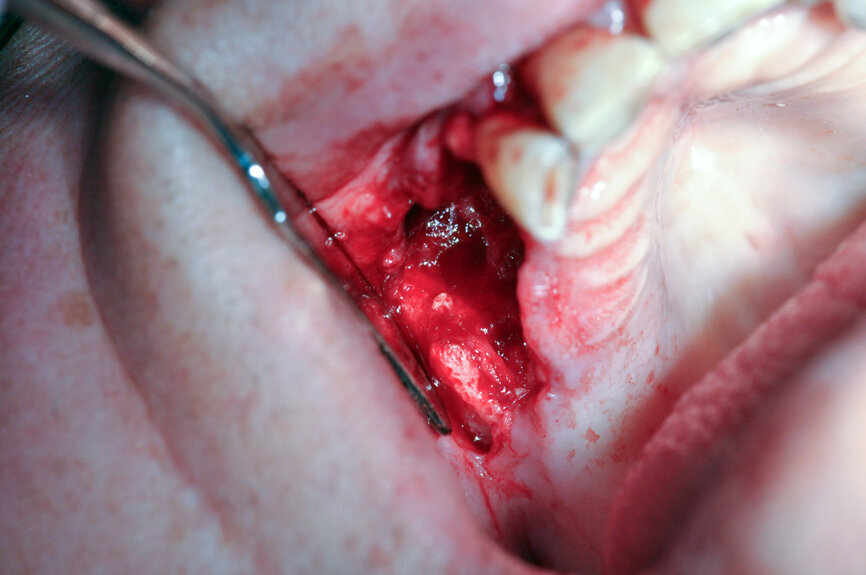

Ryc. 4_Śródzabiegowo: po chirurgii laserowej widoczna zdrowa tkanka kostna.

Ryc. 5_Śródzabiegowo: stan po zamknięciu płata.